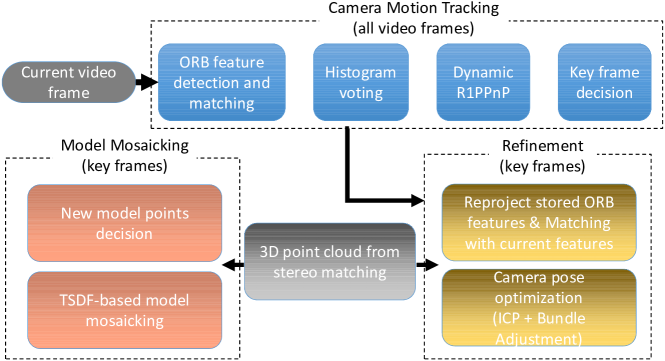

We employ the truncated signed distance field (TSDF) method [37] to mosaic the raw 3D point cloud generated from pixel disparities results of stereo matching and the camera calibration parameters to obtain the extended 3D model of the tissue surface, as shown in Fig. 3. The prerequisite to perform TSDF is to align the raw 3D point cloud accurately, which is equivalent to the estimation of camera motion in this video-based 3D reconstruction problem. As shown in Fig. 4, conventional iterative closest points (ICP)-based model alignment is difficult to handle smooth tissue surfaces. Another way to align models is based on image feature points matching. However, due to the low texture and varying illumination condition, feature matching is challenging and a large amount of outliers may exist. To overcome these problems, we propose a novel SLAM method that consists of fast and robust algorithms to handle the large percentage of feature matching outliers in real-time.

The flow chart of our SLAM method is shown in Fig. 2, which mainly consists of three modules. The first module tracks the camera motion between adjacent video frames according to ORB feature matching [38], which is mainly based on a novel and robust PP algorithm called DynamicR1PPP. The second module aims to refine the camera motion estimation results at key frames and eliminate the accumulative error, which is based on the minimization of ICP and bundle adjustment (BA) costs. The third module performs TSDF-based model mosaicking and manages feature points. In the following section, we will introduce the details of the involved algorithms.

III-A Histogram Voting-based Matching Inliers Preselection

Our SLAM system is based on the ORB feature [38], which is much faster to detect and match than the conventional SURF feature [39], and has been widely used in real-time SLAM systems, such as the ORB-SLAM method [6].

However, the low and/or repeating texture of the tissue surface and varying illumination condition may result in a large amount of incorrect feature matches. In practice we observed that the percentage of outliers may be larger than , making the traditional RANSAC+P3P[40]-based outliers removal method slow. In addition, the small number of correct matches also decreases the accuracy of camera motion estimation. Hence, it is necessary to design algorithms to handle the large percentage of matching outliers.

ORB matching is performed between two adjacent video frames for camera motion tracking. Under a reasonable assumption that the camera motion, especially the roll angle, between adjacent video frames is minimal during the surface scan, we propose to utilize the displacements of matched ORB features between two adjacent images to roughly distinguish correct and incorrect ORB matches. Specifically, we denote the image coordinates of matched ORB features at two images as and , , where and are the and image coordinates in pixels. A correct match should have a similar displacement with other correct matches. Hence, we first generate the histogram of , and then consider the ORB matches that are close to bins with large histogram value more likely to be inliers, which will be assigned with higher priority to be the control points for the subsequent DynamicR1PPP algorithm. It should be clarified that this histogram voting-based inliers preselection step may not be 100% correct, but it is fast and able to remove a large amount of outliers fast for the subsequent steps of the SLAM method.

III-B DynamicR1PPP

III-D Refinement of Camera Motion Estimation

In the camera motion tracking stage, the 3D coordinates of feature points are directly obtained from stereo matching. The estimated camera poses are not accurate enough and bundle adjustment (BA)-based refinement [41] is necessary. We also take into account the ICP-based distance between current stereo matching model and the existing model to improve the robustness of the SLAM method because feature matching with previous key frames may fail due to low texture.

We first try to match the ORB features of current key frames with those of previous key frames to eliminate accumulative error. Our SLAM algorithm stores the feature points of previous key frames for reducing the accumulative error. With the camera motion tracking results, we select several previous key frames that have enough overlapped areas with the current key frame as the candidates. Then, we perform ORB matching with the candidate previous key frames and perform DynamicR1PPP to detect correct matches.

Then we apply the optimization method to refine the camera motion estimation results. At a key frame with index , we refine the camera pose estimation results by minimizing the cost function

III-E GPU-based TSDF Mosaicking